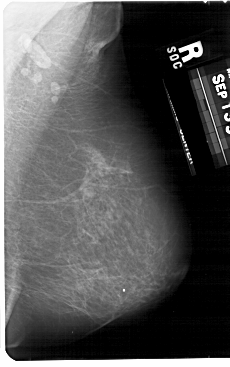

A_1676_1.RIGHT_MLO

RIGHT_CC LINES 5236 PIXELS_PER_LINE 3106 BITS_PER_PIXEL 12 RESOLUTION 43.5 NON_OVERLAY

RIGHT_MLO LINES 5491 PIXELS_PER_LINE 3436 BITS_PER_PIXEL 12 RESOLUTION 43.5 NON_OVERLAY